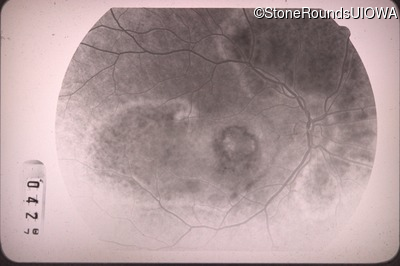

Fluorescein Angiography - Right - 20/100 -1

Exemplar